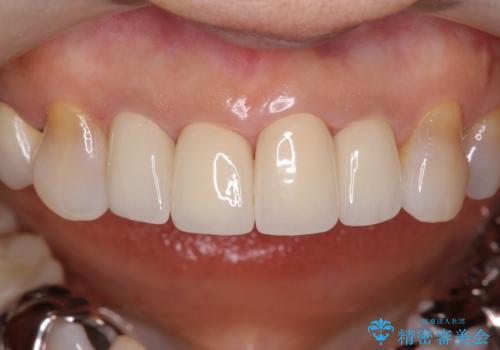

- 59.5万円 (オフィスホワイトニング 3万円、ジルコニアクラウン スタンダード 10万円×4本、仮歯 1万円×4本、精密根管治療(左上1)6万円×1本、ファイバーコア 2万円×1本)費用は治療当時の料金となります

両側の前歯もやり替えをすることで、前歯の前突感も無くしています。